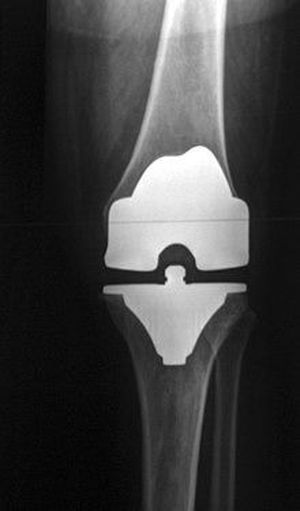

Total knee replacement